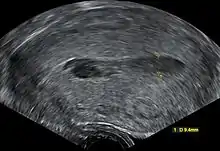

Transvaginal ultrasonography of a hematometra after childbirth, seen as a hypoechoic (darker) area within the uterine cavity. The cervix is located to the left in the image, and the fundus is located to the right.

Although hematometra can often be diagnosed based purely on the patient's history of amenorrhea and cyclic abdominal pain, as well as a palpable pelvic mass on examination, the diagnosis can be confirmed by ultrasound, which will show blood pooled in the uterus and an enlargement of the uterine cavity.[4][5] A pyelogram or laparoscopy may assist in diagnosing any congenital disorder that is suspected to be the underlying cause of the hematometra.[2]